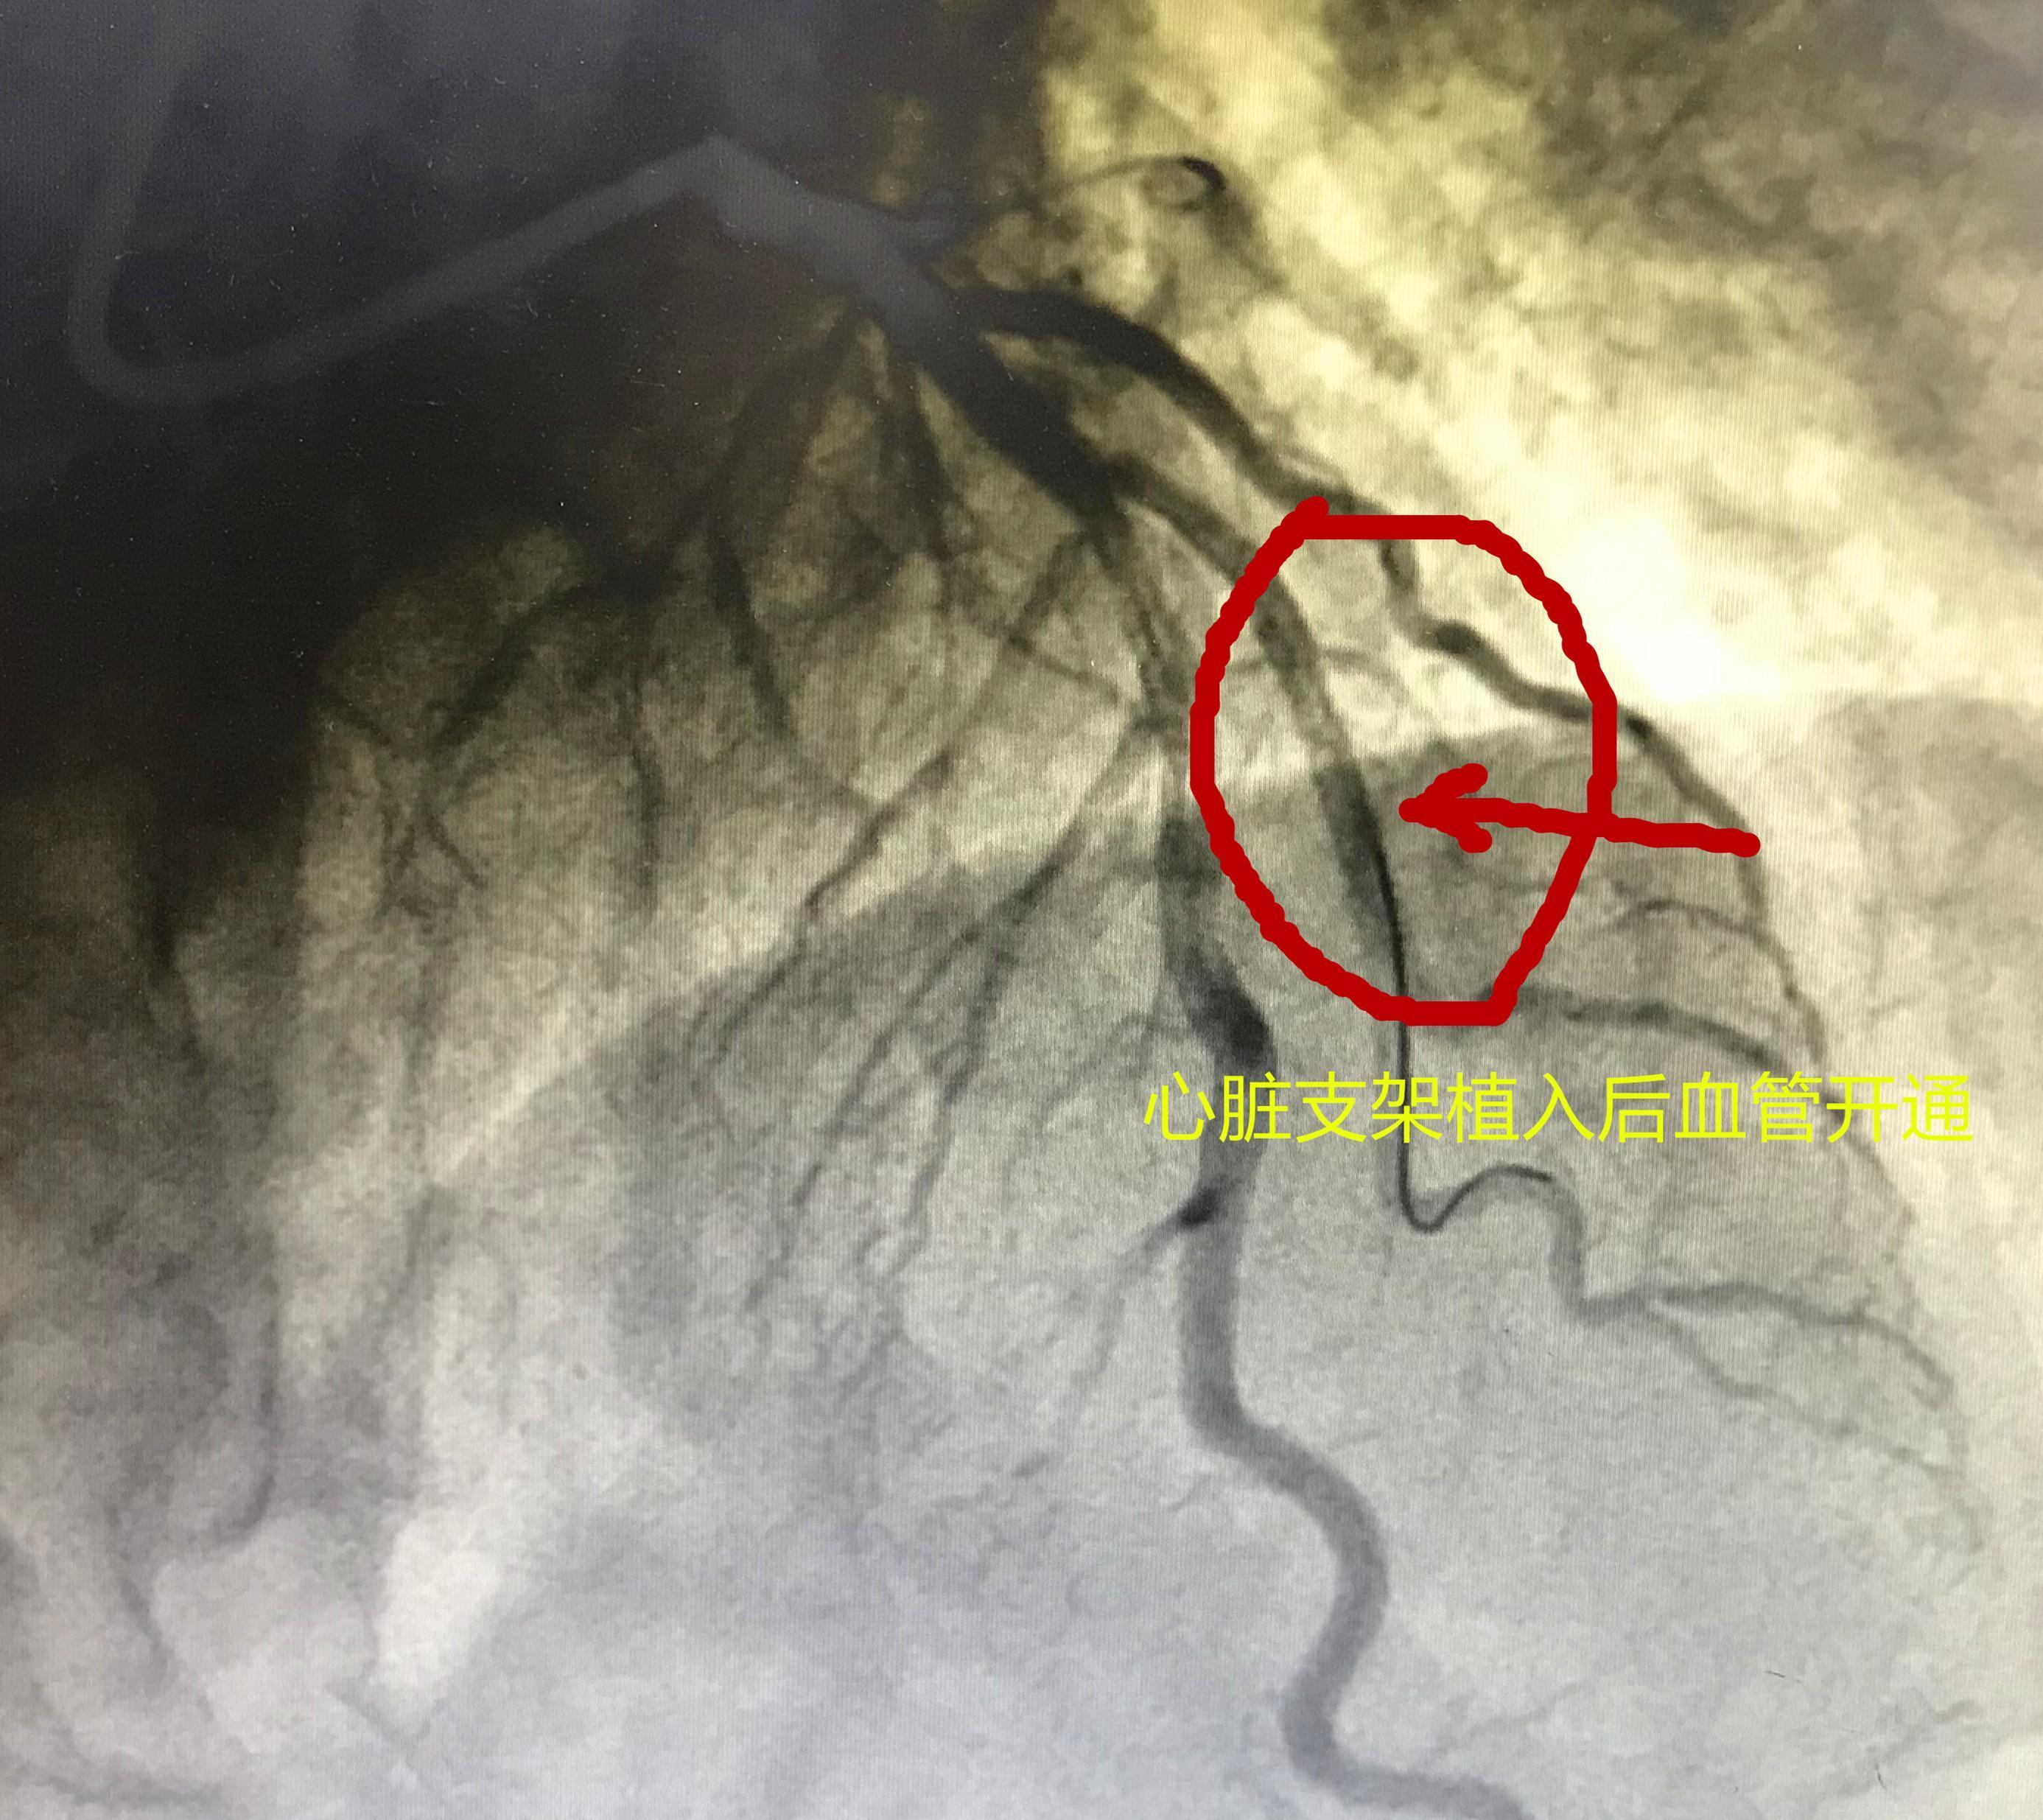

文章插图

心脏支架植入以后血管完全恢复